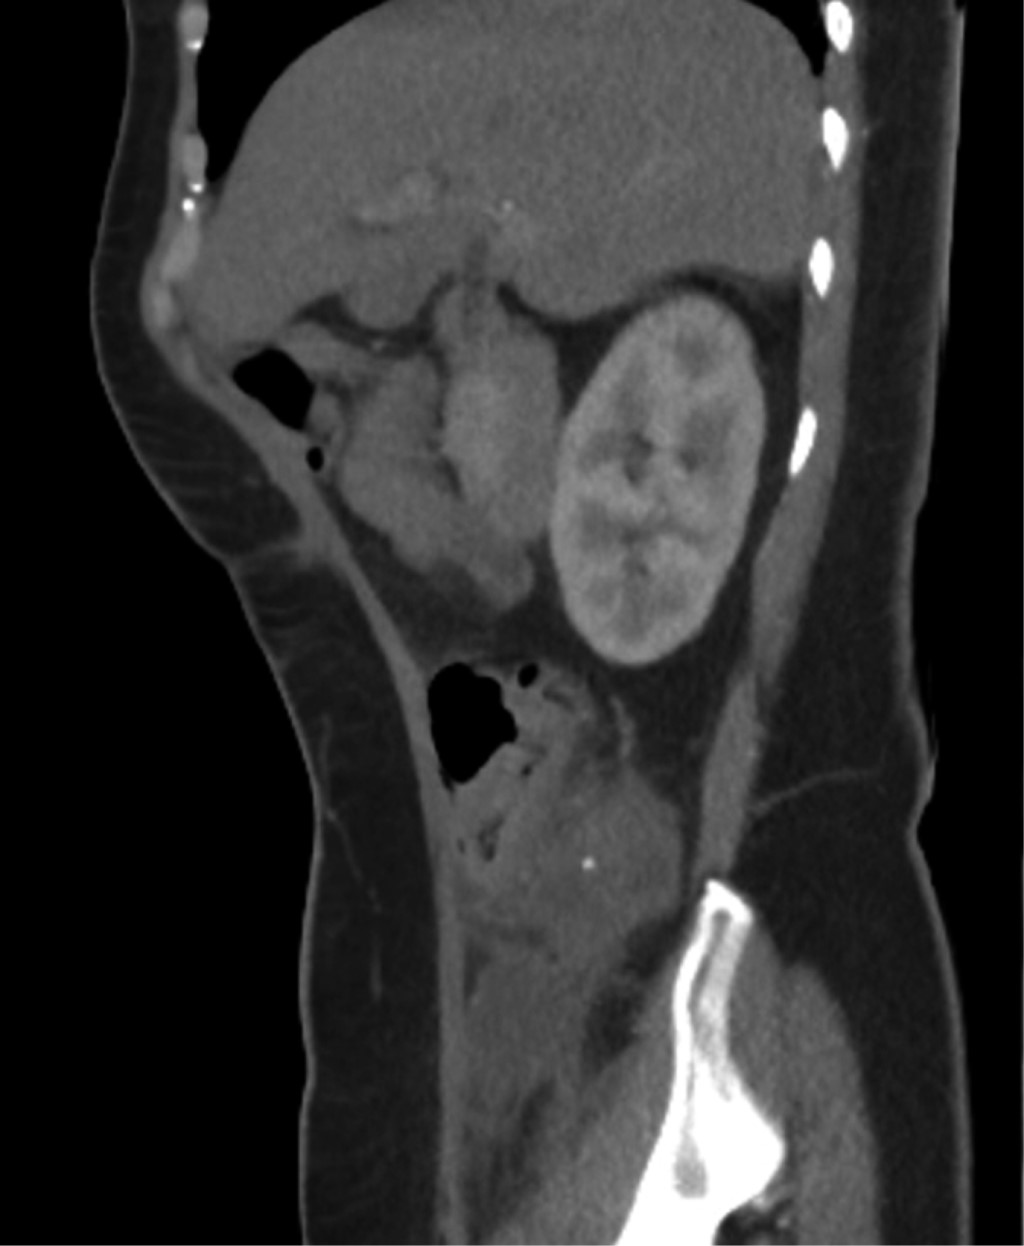

Tomografía simple y contrastada abdominopélvica 03/11/22: colección sub y retrocecal de 50 cm3 con proceso inflamatorio periférico, lo cual sugiere proceso apendicular complicado (Figuras 1 y 2).

Figura 1

Figura 2